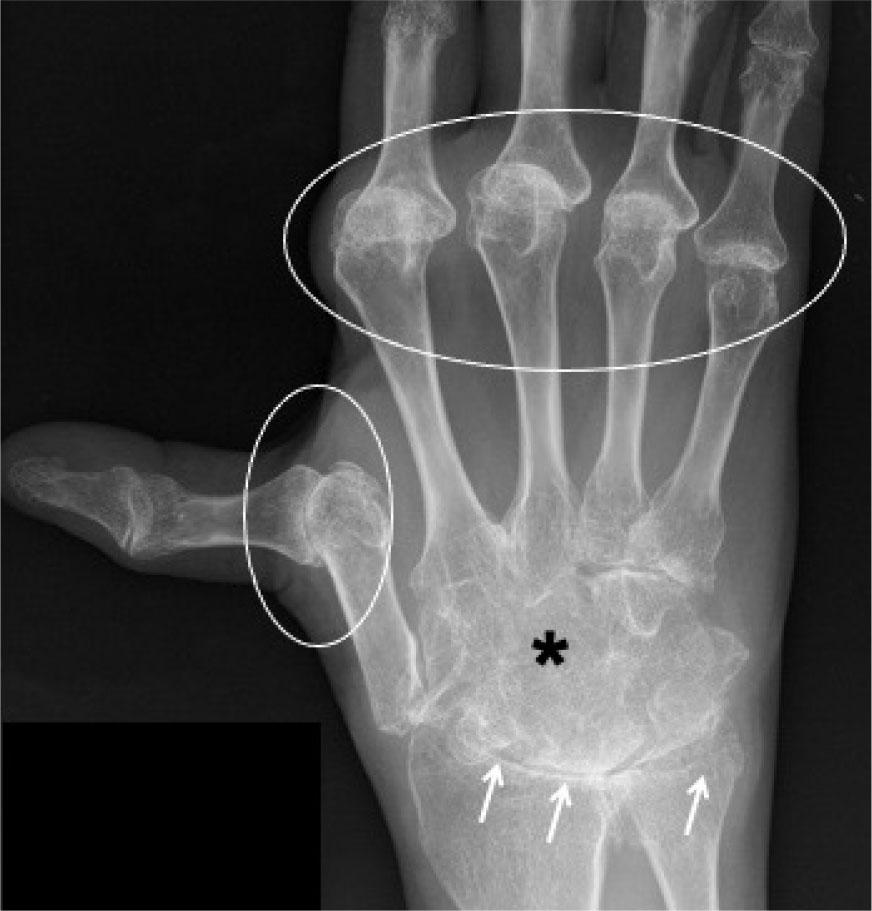

Conventional radiographs are usually the first-line imaging modality for RA. Features seen on radiographs include periarticular osteopenia, symmetrical joint space narrowing, marginal erosions, and soft tissue swelling (Fig. 1). In the early stages, the radiographs appear normal and thus, in the revised 2010 ACR/ EULAR diagnostic criteria, radiographic erosions are not included, as they represent a late stage in the disease course. US and MRI are more sensitive than radiographs and clinical examination in the early detection of disease(3), as pre-erosive synovitis can be seen in both modalities.

Fig. 1.

Rheumatoid arthritis (RA): AP radiograph of the hand demonstrates periarticular osteopenia (reduced bone density around the joints); reduced radiocarpal and intercarpal joint spaces; erosions (arrows), and subluxation of the metacarpophalangeal joints (white circles). Ankylosis of the intercarpal joints (asterisk) is seen in this case, which can be a feature of chronic untreated rheumatoid arthritis